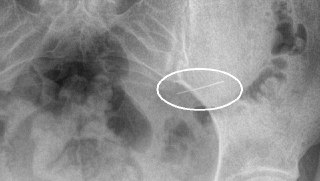

В Красногорскую больницу поступила девушка, случайно проглотившая швейную иглу. После происшествия пациентка сразу обратилась за медицинской помощью:

«Это позволило избежать дальнейшего перемещения иглы по организму. Благодаря своевременному вмешательству, опасный предмет был

благополучно удален с помощью эндоскопического оборудования», — сказал заведующий первым хирургическим отделением Николай Мурашов.